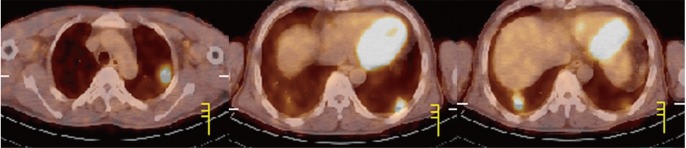

The Venereal Disease Research Laboratory (VDRL) test was positive. A diagnosis of syphilis was suspected; fluorescent treponemal antibody-absorption (FTA-ABS) and VDRL titers were assessed, resulting in reactive FTA-ABS immunoglobulin M, immunoglobulin G, and a 1 : 64 VDRL titer. A plain chest radiograph and computed tomography (CT) scan showed multiple variably sized nodules in both lungs, suggesting the possibility of a hematogenous metastatic malignancy (Fig. 1A). Screening tests for malignancy including gastrointestinal endoscopies, bronchoscopy, and CT scans of the neck, abdomen, and pelvis revealed only cervical and pancreatic lymphadenopathy. Positron emission tomography CT scanning was performed and showed hypermetabolic lesions, including the multiple pulmonary nodules, as well as the cervical and pancreatic lymph nodes, with no other organ involvement.

Figure 1

(A) Chest computed tomography scan shows multiple pulmonary nodules in both lungs. (B) After benzathine penicillin G treatment, the multiple pulmonary nodules had largely disappeared 10 months later.

Clinical information and laboratory data, including the history, physical findings, and the reactive FTA-ABS and VDRL, supported a clinical diagnosis of secondary syphilis with multiple pulmonary nodules. Thus, the patient was treated with 2.4 million units of benzathine penicillin G, injected intramuscularly. The skin lesions and lymphadenopathy resolved after 2 weeks. A follow-up chest CT scan after 1 month showed improved pulmonary nodules, which had nearly disappeared at 10 months (Fig. 1B). The VDRL titer decreased to 1 : 2 after 3 months and was nonreactive after 10 months.